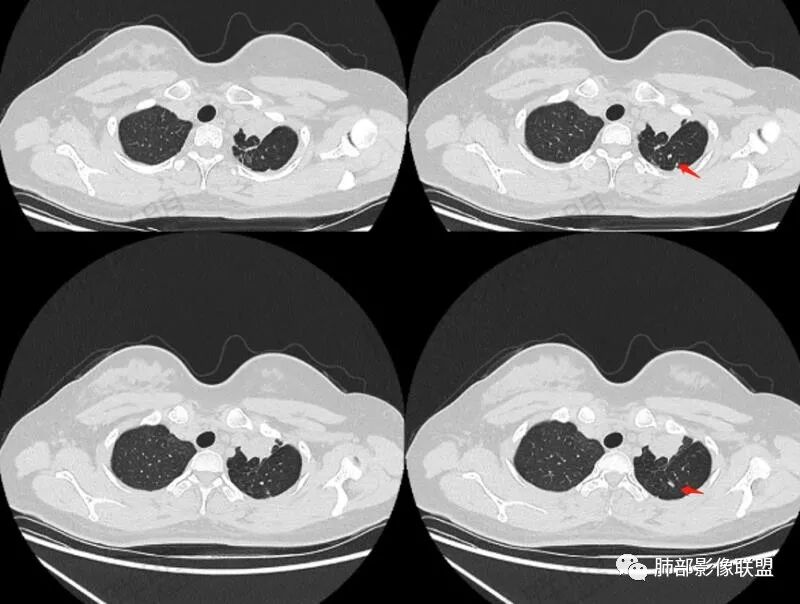

年轻女性,咳嗽咳痰一个月,左肺体积缩小,左肺尖部胸膜下实变影,宽基底与胸膜相贴,病灶边缘平直收缩,部分略膨隆,病灶下方可见支气管挤压,肺窗所示:周围伴有多发结节部分可见树丫征,纵隔窗可见病灶与纵隔胸膜黏连,部分与左肺动脉分界欠清,平扫密度尚均匀,增强扫描不均匀强化,内部可见多个低密度坏死,伴有条状血管影,纵隔淋巴结略有肿大。

女性,29岁,咳嗽咳痰,痰中带血1月余,CT示左肺尖胸膜下纵隔旁不规则实变影,内部可见小点状钙化灶,支气管略狭窄,增强可见低密度不强化区,粘液栓?实性成分明显不均匀强化,局部与左肺动脉分界不清,另左肺可见多发小结节,考虑为恶性,黏表可能,鉴别结核

青年咳嗽,左上上叶贴近纵隔胸膜一实变,外围大,和支气管关系密切,上叶支气管有狭窄后扩张再堵塞?实变大多平直收缩,局部膨隆,病灶内钙化,粘液栓,强化,周围有卫星灶,纵隔内有小淋巴结肿大,考虑结核?鉴别肿瘤

青年女性、痰血症状一月,左胸廓缩小,左上肺固有段支气管狭窄堵塞,前段支气管扩张伴粘液栓、远侧肺不张,肿块整体呈梭形沿前段支气管爬行向外延伸,内可见多处圆形低密度坏死灶,肺不张处血管造影强化明显,周围散发束状细小结节灶,肺门及纵隔淋巴结尚正常。考虑结核可能大。

4.影像显示左肺上叶支气管阻塞,左主支气管多发附壁结节影,支气管壁散在结节影更常见于结核等慢性感染。